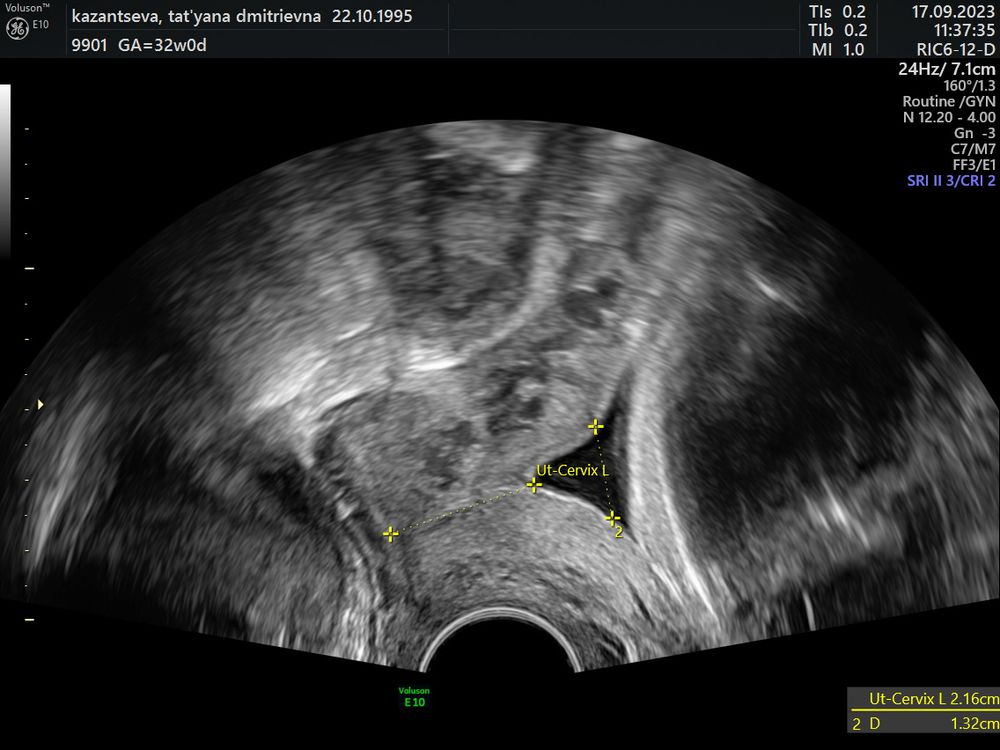

Затрудняюсь с категориейДевочки , была на узи , недкли 3 назад , была шейка матки 37 мм , внутренний зев закрыт , пошла к своему гинекологу, сказала что тянет поясница и низ живота , отправила на узи посмотреть шейку , в итоге сейчас она 22 мм , внутренний зев 3,4 , направляет в стационар, 30 нкдель , и 4 дня срок , насколько это страшно? Врач напугала до жути , чуть ли не смертью плода , если не лягу , у меня маленький ребенок , трудности в плане лечь в больницу , на сколько это серьёзно? Может что выписывали из лекарств, и что делать в таких случаях, напугала страшно , в стационар завтра поеду с утра , что там скажут

Татьяна, мне сказали , что воронкооьразная , малышка плотно прижата , внутренний зев 3,4 , нужно ехать , пессарий могут поставить сказала, либо утрожестан или как он там правильно называется прописать , и 22 мм , то что у меня тянет бывает поясница говорит матка уменьшается